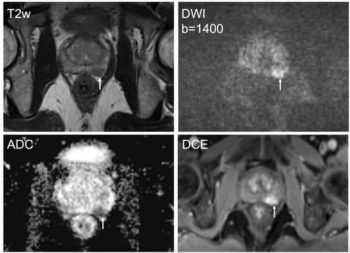

Patients with localized high-risk prostate cancer and midline radiotracer activity in the prostate had over double the incidence of urethral hyperintensity on T2W MRI, according to research presented at the American Society of Clinical Oncology (ASCO) Genitourinary Cancers Symposium (ASCO-GU).